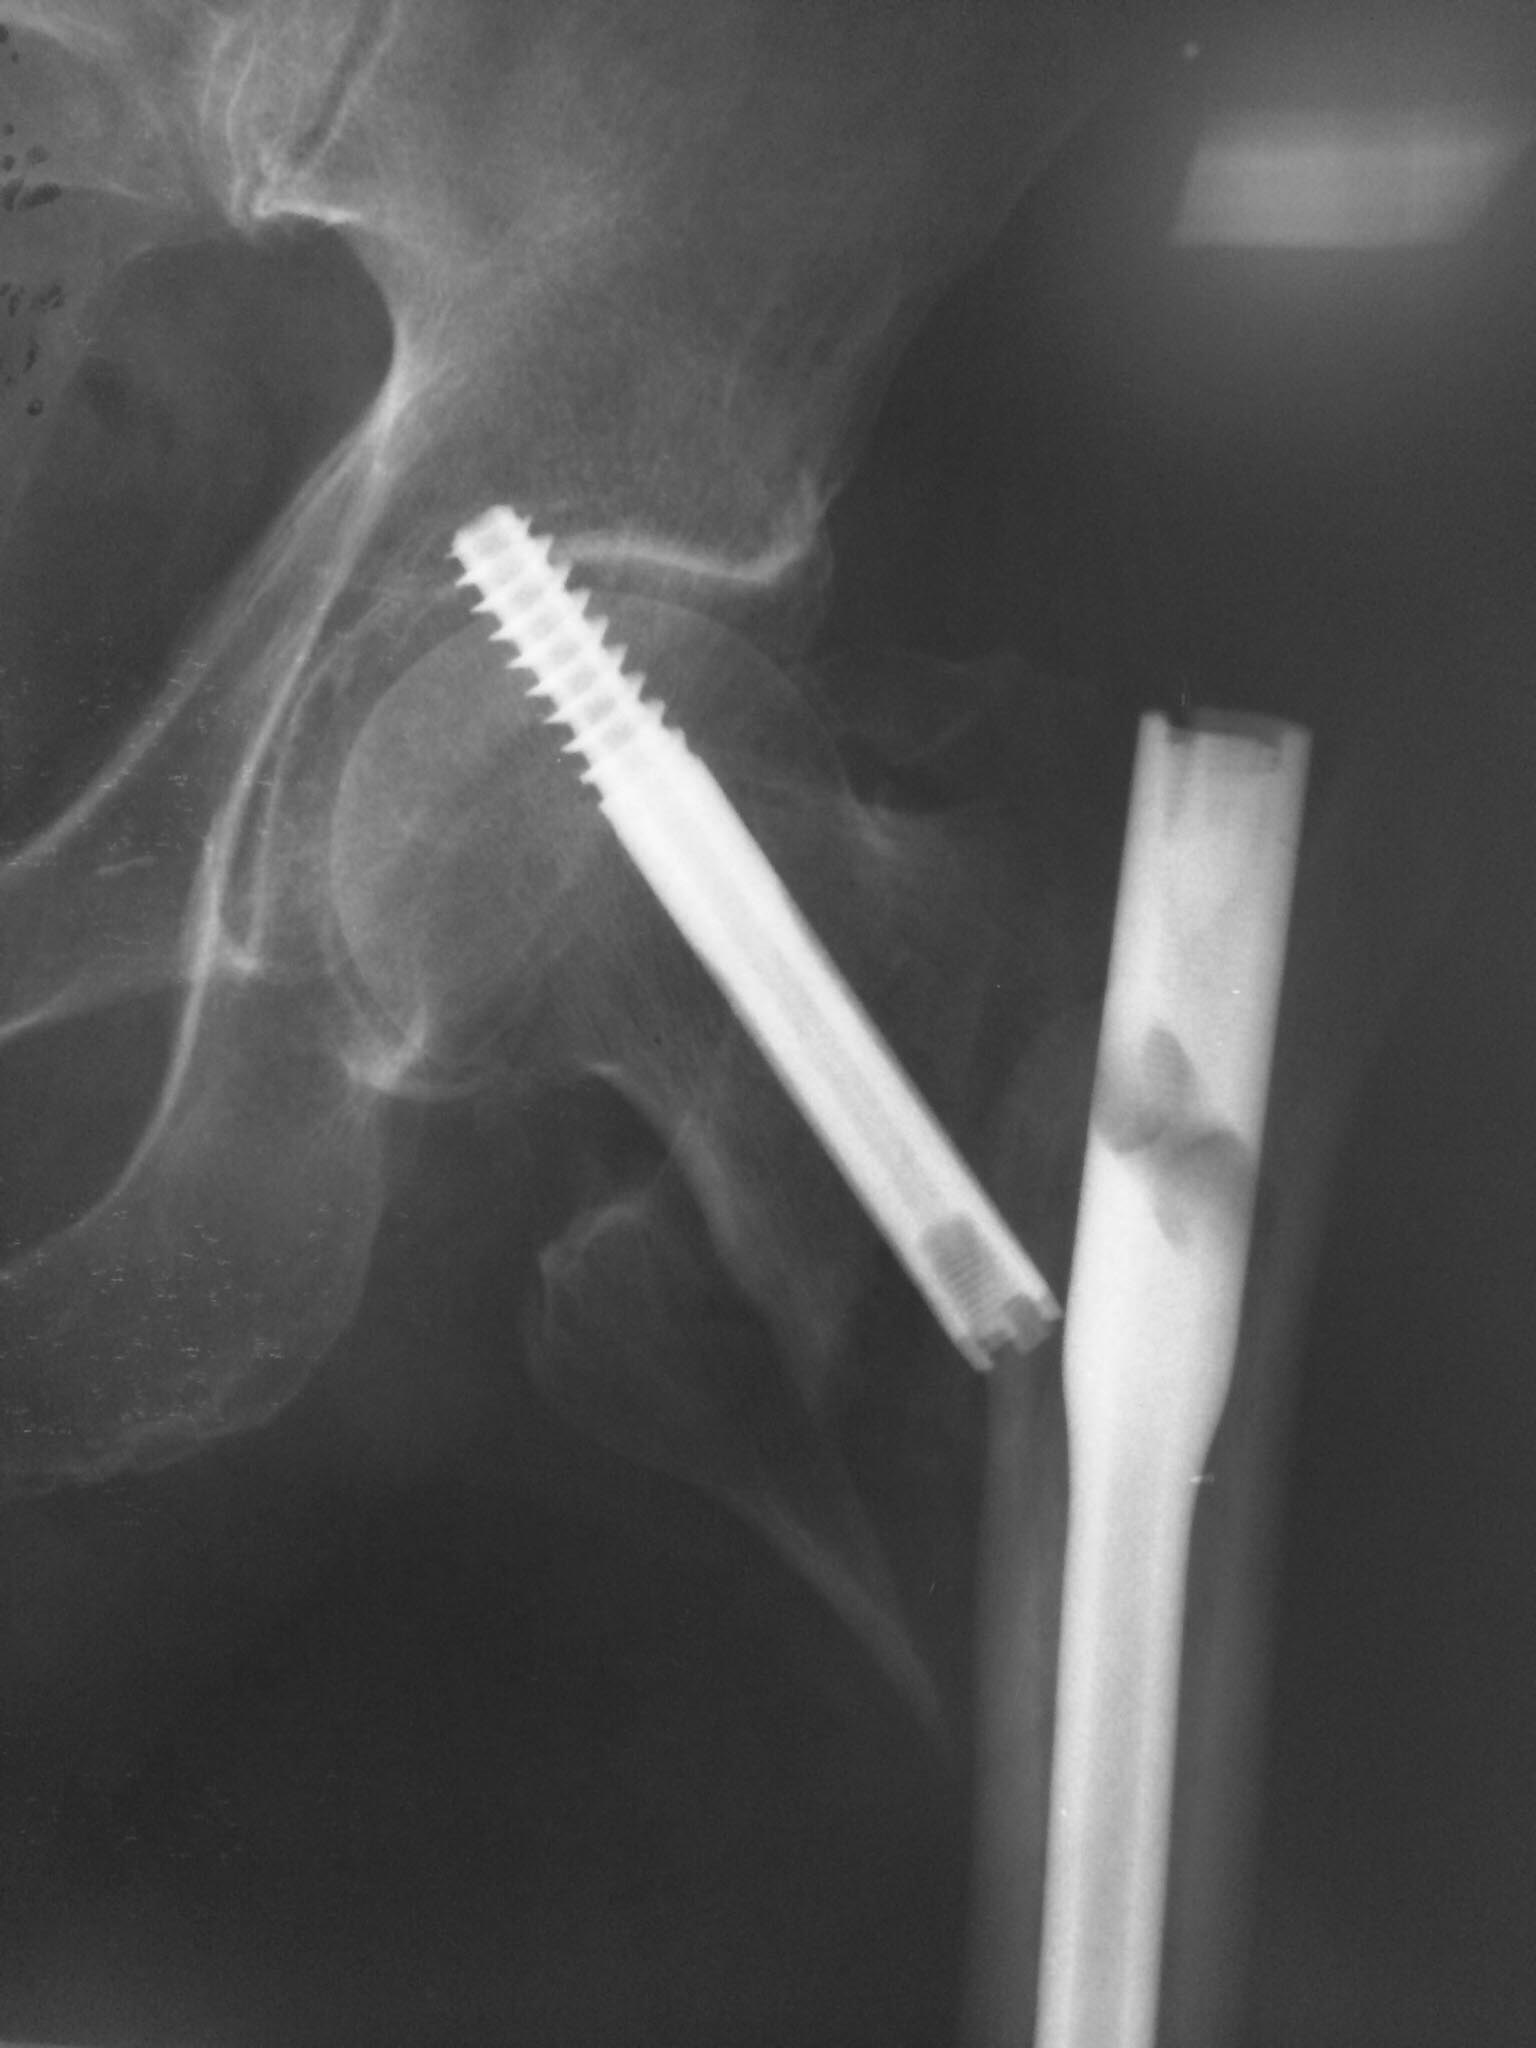

Пациентка 47 лет, нижняя параплегия, "колясочница"', но достаточно активна- самостоятельно себя обслуживает- моется в ванной, готовит и т. д. Спинальная травма у пациентки более 20 лет назад. Чувствительность до колен сохранена. В 90-х годах был выполнен остеосинтез диафизарных переломов бедра и голени с противоположность стороны пластинками. Заживлетние ран без осложнений.У нас вызывает сомнение в синтезе из-за низкого качества кости, к тому же пациентка "колясочница". Может кто-то имеет опыт в лечении таких пациентов.

По рентгенограмме по всей видимости в дополнение ко всему имеется дефект шейки бедра, поэтому мы сомневаемся будет ли синтез стабильным. Уважаемый Александр Николаевич хотелось бы узнать ваше личное мнение.

А зачем копья ломать?. Вы настроены на эндопротезирование? Так она протез вывихнет по любому, учитывая парез. Значит, либо PFN либо гамма. В гамме шеечный винт блокируется. Поэтому я бы выбрал гамму или любой интрамедуллярый гвоздь с возвожностью блокировать шеечный винт. Пусть вариант PFN, но с одним винтом и заблокировать его. Что бы не было как в приложении.( там в китайском гвозде заклинило блокирующий винт и шеечный винт не заблокировался)